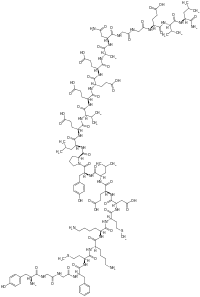

Opioid peptides

Dynorphins

Structures

| Dynorphins | ||||

|---|---|---|---|---|

Big dynorphin Big dynorphin |

Dynorphin A Dynorphin A |

Dynorphin B Dynorphin B | ||

Endomorphins

Endorphins

Structures

Enkephalins

Structures

| Enkephalins | ||||

|---|---|---|---|---|

DAMGO DAMGO |

||||

Propeptides

Others / unknown

- Adrenorphin